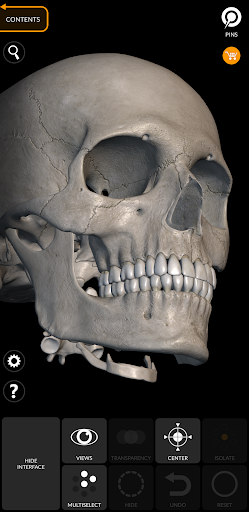

"Skeleton | 3D Atlas of Anatomy" is a next generation anatomy atlas in 3D which gives you availability of interactive highly detailed anatomical models!

Each bone of the human skeleton has been reconstructed in 3D, you can rotate and zoom in on each model and observe it in detail from any angle.

By selecting models or pins you will be shown the terms related to any specific anatomical part, you can select from 12 languages and show the terms in two languages simultaneously.

HIGHLY DETAILED ANATOMICAL 3D MODELS

• Accurate 3D modeling

• Surfaces of the skeleton with high resolution textures up to 4K

• Rotate and Zoom every model in the 3D space